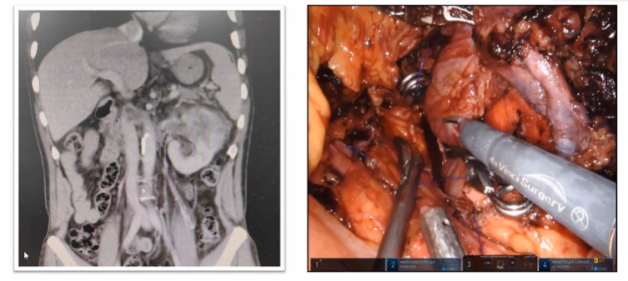

下腔静脉节段性切除术-完全腔镜封闭式En-block技术

既往在开放手术中很少做下腔静脉节段性切除,但随着经验不断增加,我们发现其实在腔镜下,腔静脉的节段性切除更加方便,在下腔静脉远心端进行对侧静脉切除完全可以在直视下完成,大大降低了手术难度,所以我们把原来的开放术式变成了完全腔镜En-block切除。

如下图所示,该病例瘤栓充满整个下腔静脉,同时长满血栓,对于该病例我们采用全封闭式的En-block切除,首先是离断下腔静脉,翻起来以后去找寻右肾动脉,切断右肾动脉以后再把左肾静脉切断,然后一直沿着瘤栓向肝后寻找游离肝门后方腔静脉。既往类似病例中肝门后方腔静脉很难暴露清楚,但是有了机器人助力,使其充分显露出来就变的相对容易很多。肝后下腔静脉经过充分游离后,再将瘤栓全部挤压进入腔静脉中,然后探查至无瘤栓处,直线切断腔静脉,将瘤栓取出。完全封闭式的瘤栓取出,可以获得很好的操作空间。该病例曾在2023年4月在第8届泌尿生殖系统研讨会上进行演示。